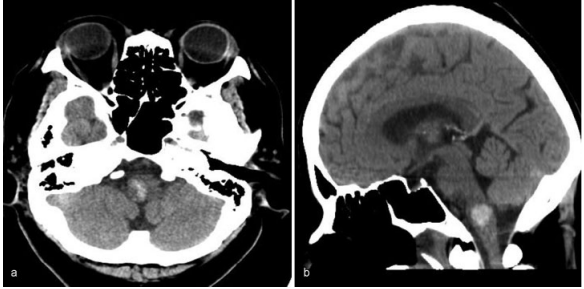

其中,一位70岁的老人因为突然出现恶心和呕吐而被转诊到巴教授所在医院。右舌下神经麻导致右舌偏斜。她的血压是201/100毫米汞柱。电脑断层扫描(CT)显示右侧延髓出血。

图:右侧延髓出血的电脑断层影像,(a)轴向(b)矢状面。

入院后,她出现白天呼吸抑制(每分钟呼吸10次)和夜间呼吸暂停。然后她进行插管,并用呼吸机控制呼吸。MRI未发现明显的出血原因,如海绵状畸形、动静脉畸形或肿瘤。患者随后被诊断为高血压原发性延髓出血,随后通过持续静脉输入钙通道阻滞剂来降低血压。然而,病人的呼吸抑制没有改善。